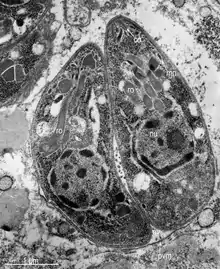

In its lifecycle, T. gondii adopts several forms.[32] Tachyzoites are responsible for acute infection; they divide rapidly and spread through the tissues of the body. Tachyzoites are also known as "tachyzoic merozoites", a descriptive term that conveys more precisely the parasitological nature of this stage.[33] After proliferating, tachyzoites convert into bradyzoites, which are inside latent intracellular tissue cysts that form mainly in the muscles and brain. The formation of cysts is in part triggered by the pressure of the host immune system.[34] The bradyzoites (also called "bradyzoic merozoites") are not responsive to antibiotics. Bradyzoites, once formed, can remain in the tissues for the lifespan of the host. In a healthy host, if some bradyzoites convert back into active tachyzoites, the immune system will quickly destroy them. However, in immunocompromised individuals, or in fetuses, which lack a developed immune system, the tachyzoites can run rampant and cause significant neurological damage.[32]

The parasite's survival is dependent on a balance between host survival and parasite proliferation.[34] T. gondii achieves this balance by manipulating the host's immune response, reducing the host's immune response, and enhancing the parasite's reproductive advantage.[34] Once it infects a normal host cell, it resists damage caused by the host's immune system, and changes the host's immune processes.[35] As it forces its way into the host cell, the parasite forms a parasitophorous vacuole (PV) membrane from the membrane of the host cell.[2][36] The PV encapsulates the parasite, and is both resistant to the activity of the endolysosomal system, and can take control of the host's mitochondria and endoplasmic reticulum.[2][36]

When first invading the cell, the parasite releases ROP proteins from the bulb of the rhoptry organelle.[2] These proteins translocate to the nucleus and the surface of the PV membrane where they can activate STAT pathways to modulate the expression of cytokines at the transcriptional level, bind and inactivate PV membrane destroying IRG proteins, among other possible effects.[2][36][37] Additionally, certain strains of T. gondii can secrete a protein known as GRA15, activating the NF-κB pathway, which upregulates the pro-inflammatory cytokine IL-12 in the early immune response, possibly leading to the parasite's latent phase.[2] The parasite's ability to secrete these proteins depends on its genotype and affects its virulence.[2][37]